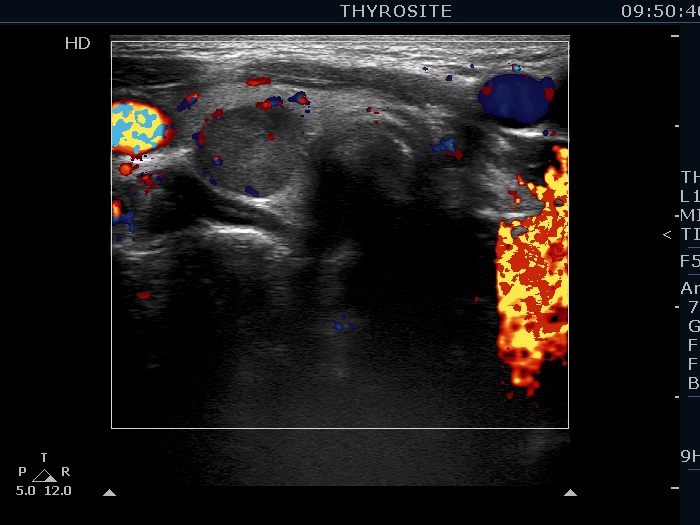

Right lobe, longitudinal scan

Left lobe, transverse scan, color Doppler mode. The lesion has central, intralesional vascularity.